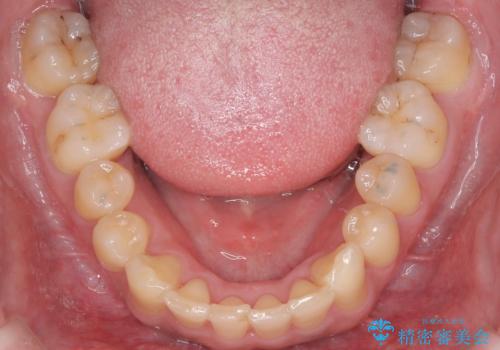

今回の矯正治療では、まず歯が並ぶスペースを確保するため、上顎の小臼歯を抜歯しました。抜歯によってできたスペースを利用して前歯を奥へ移動させ、デコボコを解消。同時に、奥歯の咬み合わせを調整することで、深すぎた咬み合わせであるディープバイトも改善しました。治療の結果、長年気にされていた前歯のデコボコが解消され、理想的な歯並びに。さらに、正しい咬み合わせを獲得したことで、機能的にも安定した美しい口元になりました。